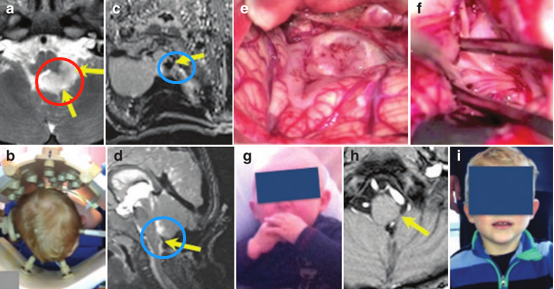

腦干延髓膠質(zhì)瘤高治愈案例:手術(shù)前3天正好是女兒的5歲生日,過(guò)生日當(dāng)天我們?nèi)胰诵那槌林?,本?lái)以為這可能是孩子的較后一個(gè)生日,想不到幸運(yùn)之神就...

2021年,年僅10歲的果果因發(fā)燒、肺炎查出延髓占位性病變。行腫瘤切除術(shù),術(shù)后二天在PICU氣管切開(kāi),術(shù)后病理(多形性黃色星形細(xì)胞瘤)。手術(shù)后癥狀稍微...

他(國(guó)內(nèi)神經(jīng)外科醫(yī)生)正好也是在德國(guó)跟過(guò)巴教授,我從他的分析和溝通過(guò)程中,包括結(jié)合巴教授的回復(fù),我就決定了這個(gè)事情。所以,按教授的原話來(lái)...